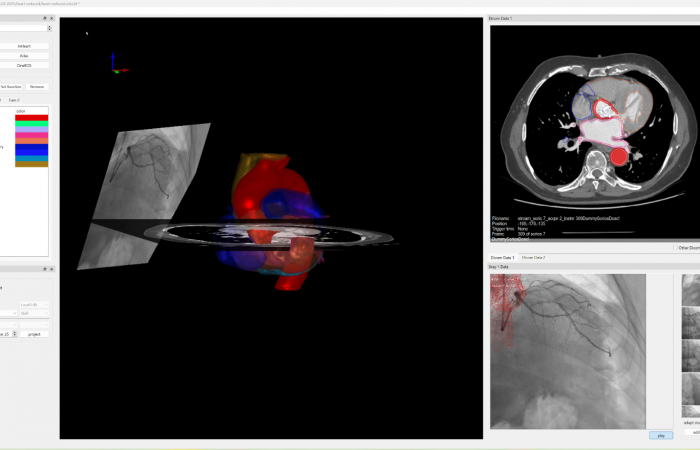

Pracownia Funkcjonalnego i Wirtualnego Medycznego Obrazowania 3D (Pracownia 3D-FM) funkcjonuje w strukturze Zakładu Diagnostyki Obrazowej Szpitala Uniwersyteckiego w Krakowie pod kierownictwem Prof. dr hab. Tadeusza Popieli. Jej celem jest opracowanie i wdrożenie innowacyjnych metod przetwarzania oraz analizy sygnałów i obrazów medycznych, w tym wykorzystanie technologii rzeczywistości wirtualnej oraz metod obrazowania funkcjonalnego. Rozwiązania te wspierają przedoperacyjne planowanie, monitorowanie procedur medycznych oraz wzbogacają proces diagnostyczny o nowe formy wizualizacji danych medycznych.

Pracownia 3D-FM zajmuje się m.in. następującymi obszarami:

- Tworzeniem modeli 3D do celów przedoperacyjnego planowania oraz wizualizacji diagnostycznej.

- Rozwojem rozwiązań programowych do obrazowania medycznego.

- Integracją urządzeń i systemów diagnostycznych (PACS, RIS, HIS, OIS) z infrastrukturą szpitalną, umożliwiającą efektywne zarządzanie danymi obrazowymi i funkcjonalnymi.

- Obrazowanie Medyczne 3D

- Segmentacja i analiza danych DICOM

- Rekonstrukcja danych medycznych

- Technologie immersyjne (mieszana, rozszerzona i wirtualna rzeczywistość)

- Obrazowanie funkcjonalne

- Elektrokardiograficzne obrazowanie 3D (ECGI)